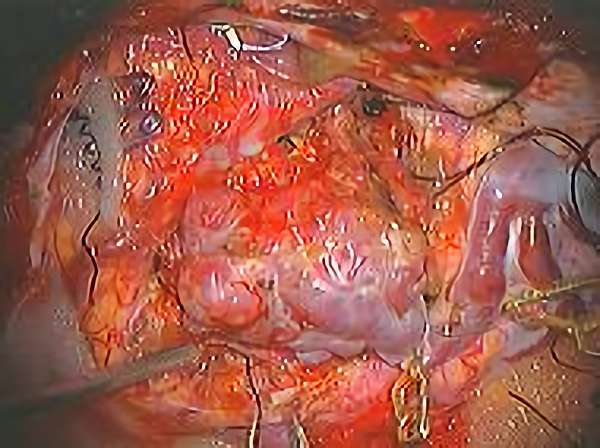

No.359 モニタリング

No.359 手術前

No.359 手術中

No.359 手術後

出血既往があり。2回の手術前血管内手術の後に、

Lateral transpeduncular approachにより再々出血予防を目的に

摘出手術を行う。完全摘出であることを確認した。

手術による合併症や後遺症なしで退院した。経過良好。